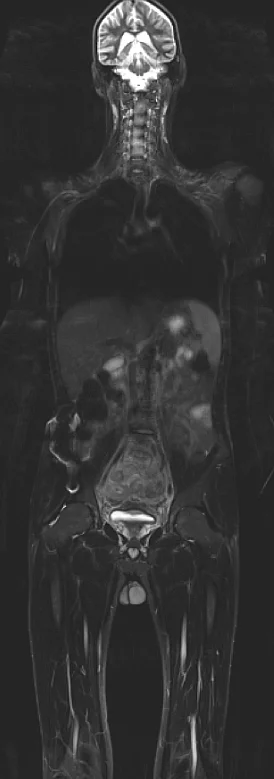

Magnetresonanztomographie: Gesamtes Spektrum der MRT-Diagnostik

- MRT Diagnostik des Halses, Brustkorbes, Bauchraumes und Beckens

- MR Angiographie des gesamten Gefäßsystems

- Ganzkörper MRT

In der Abteilung für Radiologie stehen zwei MR-Tomographen zur Verfügung. Es werden Spezialuntersuchungen wie die Ganzkörper-MRT, MR Mammographie, multiparametrische Prostata-MRT oder Kardio-MRT durchgeführt (siehe Leistungsspektrum).